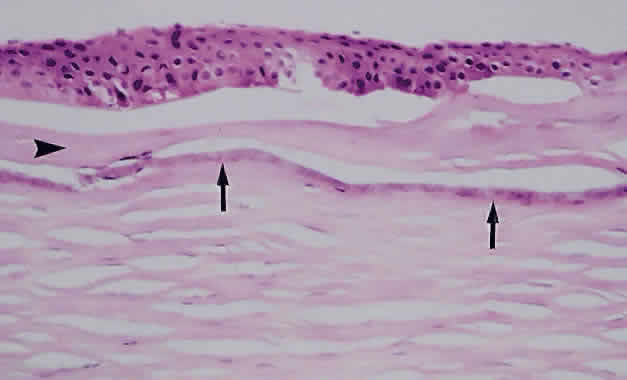

The corneal endothelium functions to maintain a state of relative dehydration of the corneal stroma, which permits the orderly arrangement of the stromal lamellae and, thus, transparency.150 Because the corneal endothelium does not regenerate, loss of endothelial cells results in the enlargement of adjacent endothelial cells to compensate. With continued damage and loss, these enlarged cells are unable to maintain the required degree of fluid transport and corneal edema results, eventually involving the entire stroma and finally the epithelium (Fig. 16).150 Edema of the corneal epithelium results in the failure of the hemidesmosomes between the basal epithelium and Bowman's membrane, with subsequent bullae formation. Bullae may rupture, and eventually a fibrovascular tissue grows to cover the defect, resulting in corneal scarring (Fig. 17).

Fig. 17. A. Limbal region of an eye enucleated after endophthalmitis showing angle closure due to peripheral anterior synechiae as well as a chronic inflammatory cell infiltrate within the iris (hematoxylin and eosin; × 31). B. Fibrovascular pannus ingrowth along Bowman's layer of the cornea (hematoxylin and eosin; × 200).